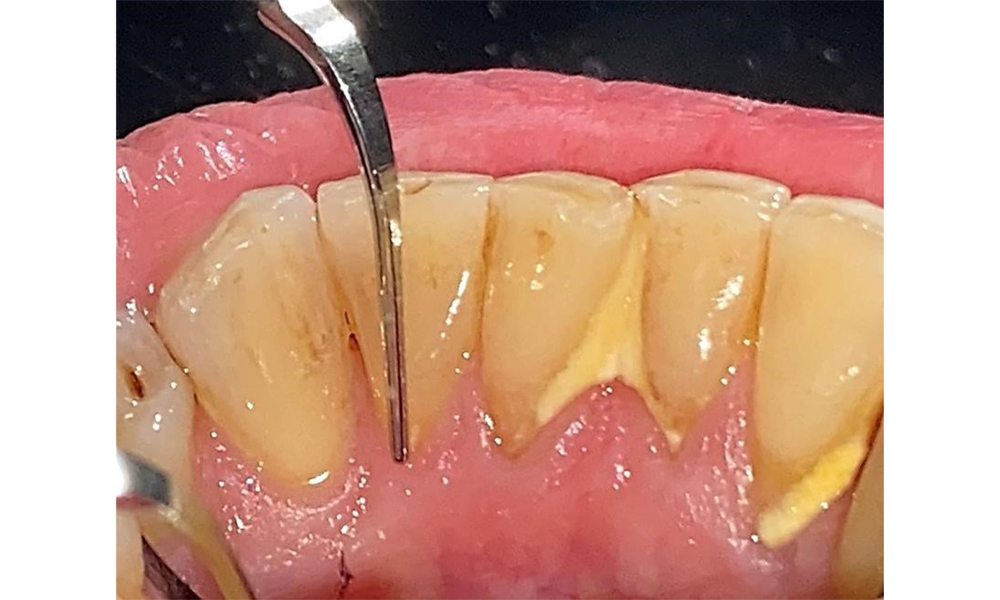

The patient has stage II, grade B periodontitis (5). At 1 to 3 mm, the clinical probing depths were within the physiological range. Localized probing depths of 5 mm were observed on the mesiopalatal aspects on both 17 and 27. There are generalized recessions of 1–3 mm with partial loss of the interdental papillae (Fig. 2, Fig. 3, Fig. 4)

The patient uses interdental brushes and an electric toothbrush. This demonstrates good compliance and good intraoral hygiene behaviour and understanding at home. Regular motivation and re-instruction are indispensable due to the risk of progression, particularly with regard to the cleaning of interdental areas, since increased probing depths were detected in these areas. Localized calculus and soft plaque was present in the lingual anterior mandibular region, and these must be shown to the patient. The interdental brush size may need to be checked and adjusted. A soft brush attachment is recommended based on the presence of exposed root surfaces to prevent wedge-shaped defects. Toothpaste with a low abrasive value should be used.

There are no limitations regarding the choice of instrumentation methods. Regular supragingival and subgingival instrumentation is essential to prevent disease progression due to the pre-existing periodontitis and high risk of recurrence. There are no limitations placed on the selection of instruments for mechanical biofilm removal from a general medical perspective, and removal should be performed as needed. Hard and mineralized plaque, such as calculus and concretions, should be removed using manual instruments or sonic/ultrasonic scalers (Fig. 9) (8, 9).